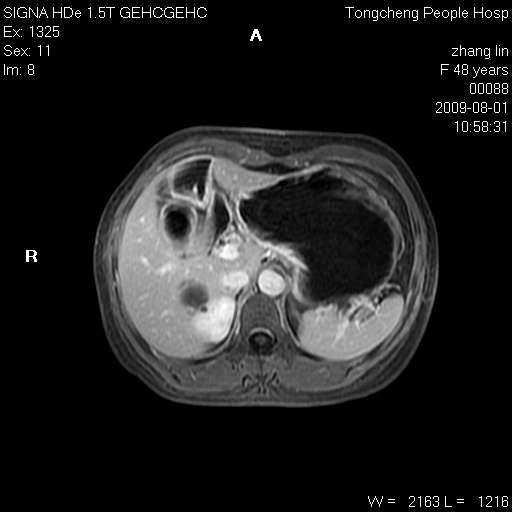

女,48岁。健康体检,彩超发现右肾占位性病变。平素健康。

临床诊断:右肾占位性病变,性质待定(囊肿?肿瘤?)。

上中腹部mr平扫+增强扫描,图像如下:

右肾上极见一类圆形病灶,t1wi呈等信号t2wi呈等高混杂信号,三期增强无强化,边界清---考虑囊肿出血。

同反相位均表现为等信号,病变无强化,考虑含蛋白的囊肿可能,弥散加权相或许有些帮助,

肝囊肿

慢性胆囊炎